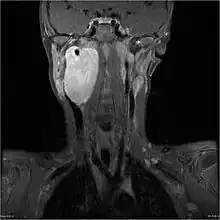

MRI of a ganglioneuroblastoma found in the head and neck of a 7 year old Caucasian male. | |